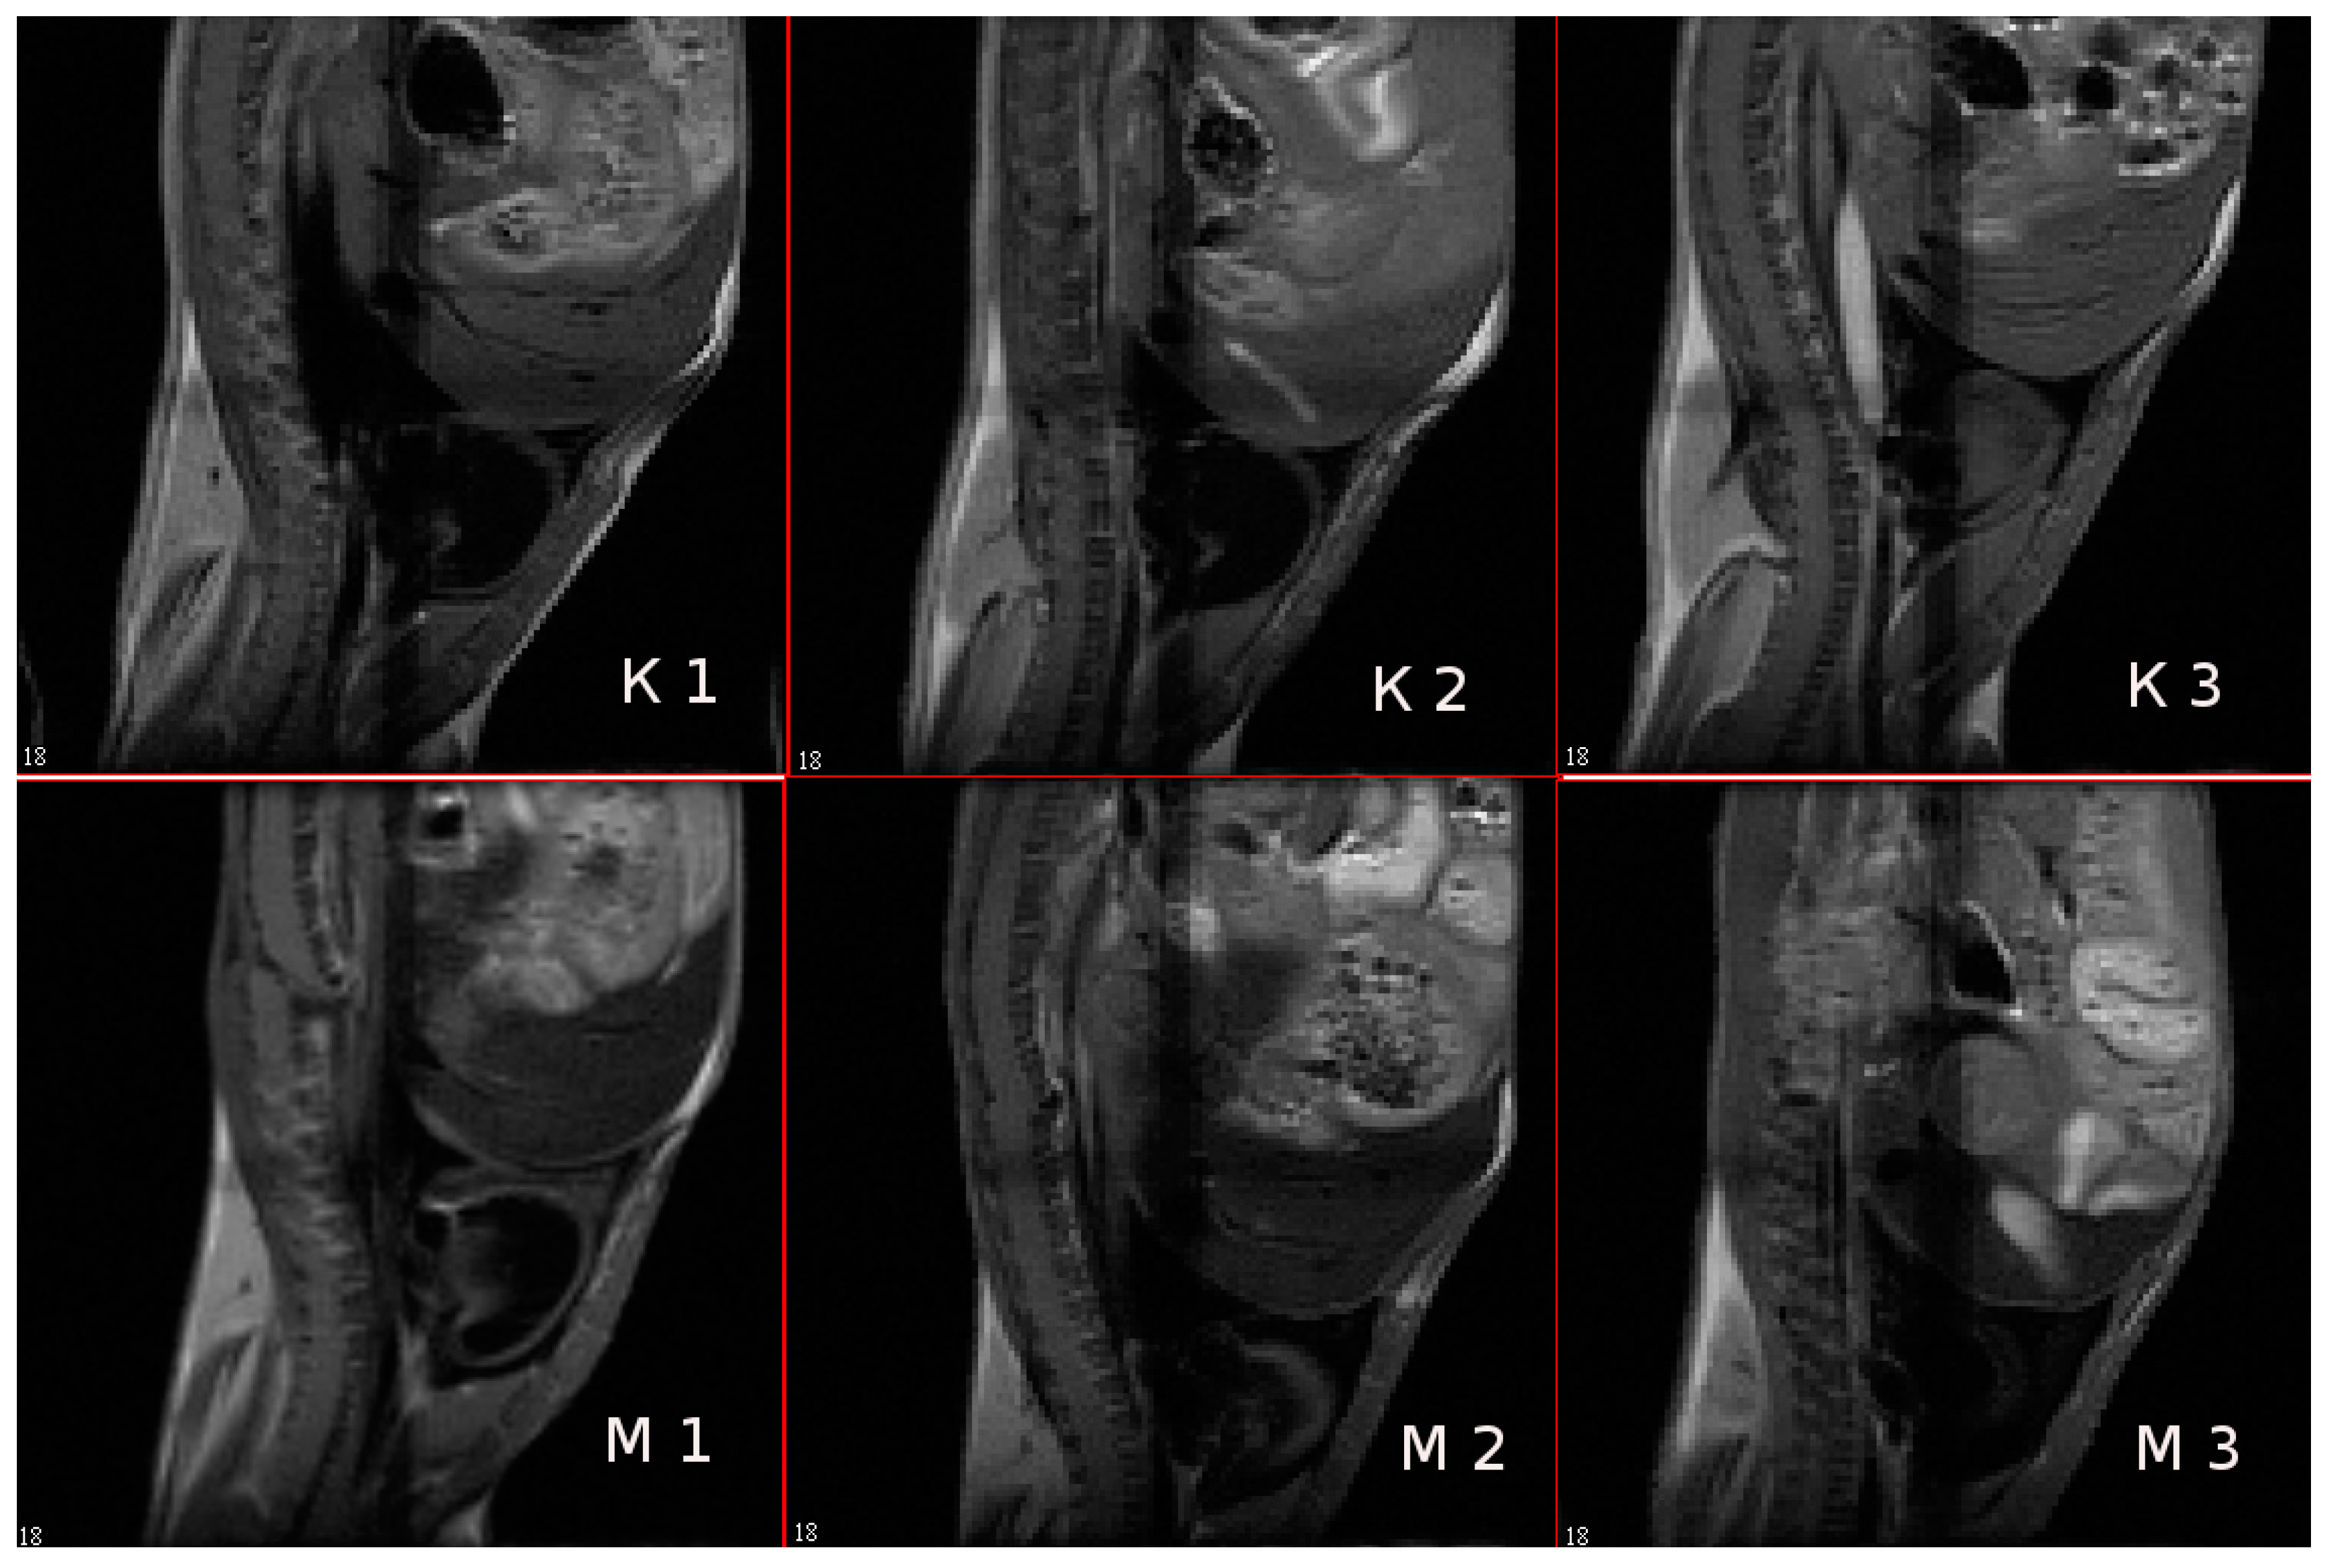

3.9. In Vivo MR-Contrast Enhancing Properties of SPIONs@IFNα-2b Conjugates